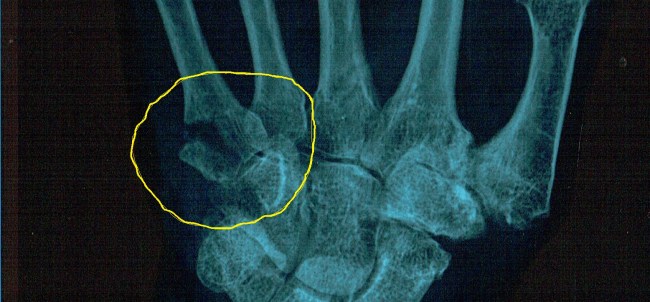

The broken piece of bone you can see in the x-ray was of concern to the doctor at the clinic and he recommended further examination by an expert. I found one at St Vincent Hospital and for a fistful of dollars was examined and given the advice that it would be best to leave things as they were because it was so long since the accident – five weeks at this point. Pinning it would be difficult, painful and take up to six weeks to heal. For a few dollars more I had a session with a physiotherapist who, the cast now having been removed, put my hand in a lightweight splint and gave me some exercises to do. They worked too. The tendons across the knuckles slowly stretched back to normal and over the next few weeks I regained full movement in my fingers. My shoulder was back to normal too and I felt I was ready to organise a return to Innamincka and a reunion with Doris.

Damaged collarbone joint. Just one of the injuries.